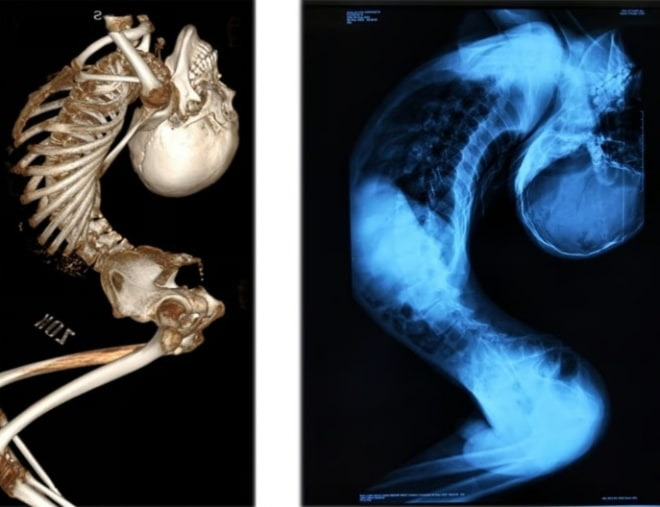

폴더 소년의 이야기는 많은 사람들에게 감동을 주었습니다. 그의 회복 과정은 단순한 신체적 변화뿐만 아니라, 희망과 용기의 상징으로 여겨졌습니다. 많은 이들이 그의 이야기를 통해 장애에 대한 인식을 새롭게 하고, 서로를 이해하는 계기가 되기를 바랍니다.

폴더 소년의 이야기는 우리에게 많은 것을 시사합니다. 장애를 가진 사람들도 희망을 잃지 않고, 자신의 삶을 변화시킬 수 있다는 메시지를 전하고 있습니다. 앞으로도 그의 이야기가 많은 이들에게 영감을 주기를 바랍니다.